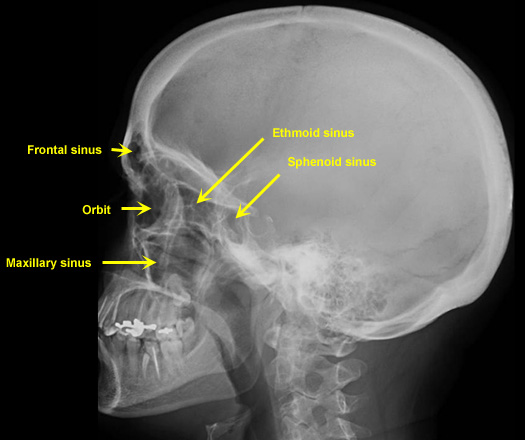

Plain Films of Skull and Spine